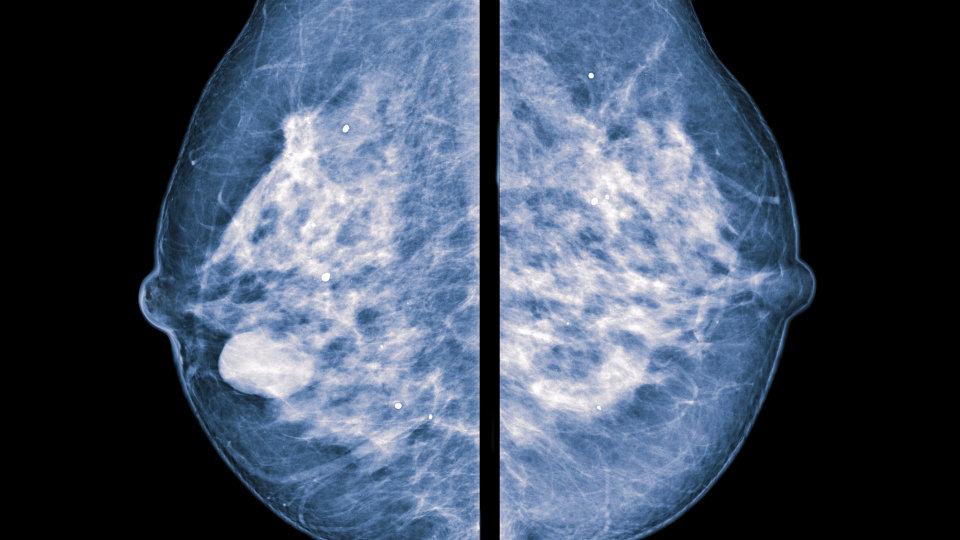

The Tumour Environment Can Affect Breast Cancer Prognosis

The environment in which breast cancer arises –the interplay between the patient’s BMI, tumour size and cancer-specific proteins –is of importance for the prognosis.

The environment in which breast cancer arises –the interplay between the patient’s BMI, tumour size and cancer-specific proteins –is of importance for the prognosis. This is shown in a study from Lund University in Sweden. The knowledge could further enhance precision medicine in breast cancer.